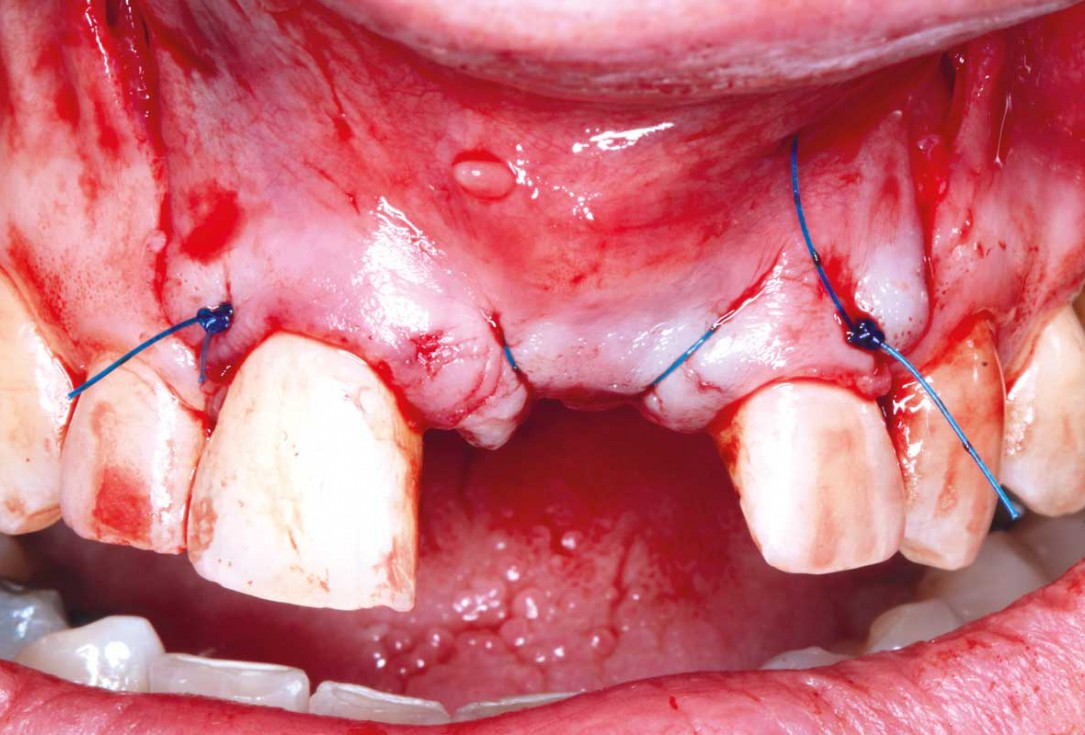

5/35 - Three-sided full thickness flap and cleaning the surgical area from the granulation tissueBlock grafting in the aesthetic zone with maxgraft®, Jason® membrane and cerabone® - Dres. H. Maghaireh and V. Ivancheva

6/35 - Three-sided full thickness flap and cleaning the surgical area from the granulation tissueBlock grafting in the aesthetic zone with maxgraft®, Jason® membrane and cerabone® - Dres. H. Maghaireh and V. Ivancheva